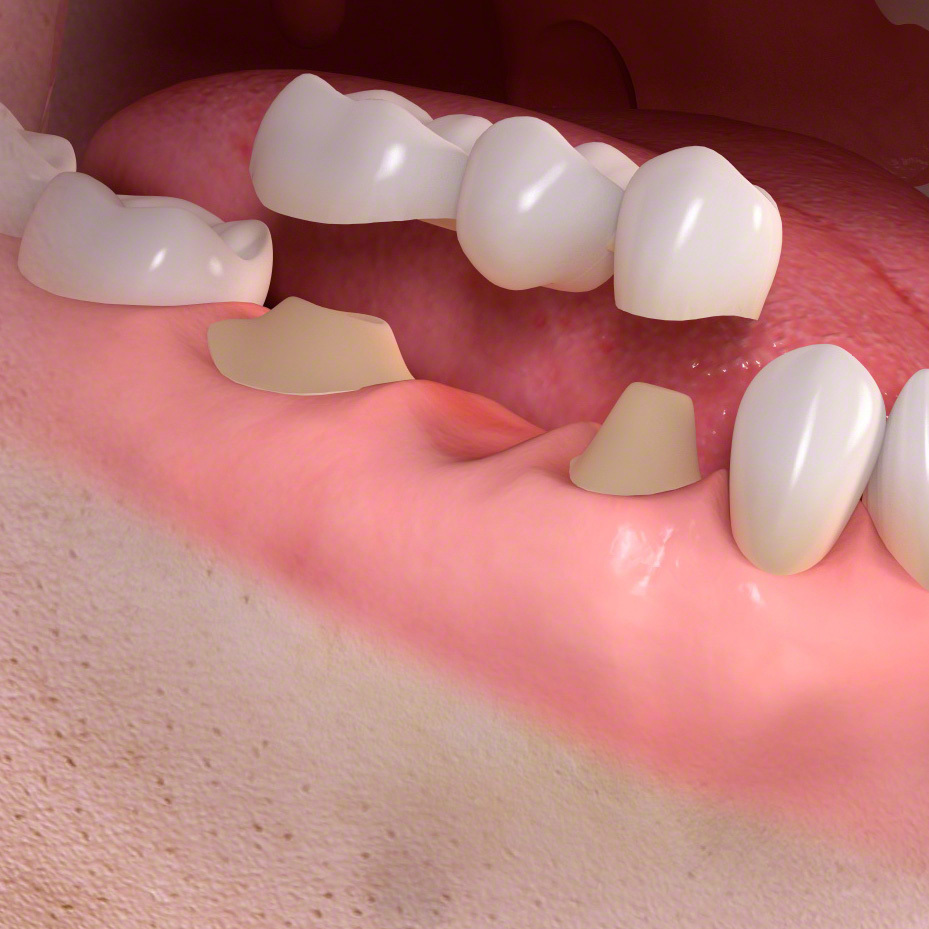

抜歯後の三つの治療法

前歯を失った時 インプラントのススメ

奥歯を失った時 インプラントのススメ

インプラントとその他の治療

入れ歯、ブリッジ、インプラントを選択できるケースがあります。患者さんのご要望を最も反映できる治療法を提案することが可能です。

歯の欠損

歯を再生する時、インプラントは前後の歯に固定源を求めない唯一の治療法になります。自費治療になります。

ブリッジ

・健康な歯であっても、土台にするために小さく歯を削る必要があります。

ブリッジは少数の歯を失った時に行う治療法です。

前後の土台になる歯が平行に生えている場合のみ可能な治療法です。